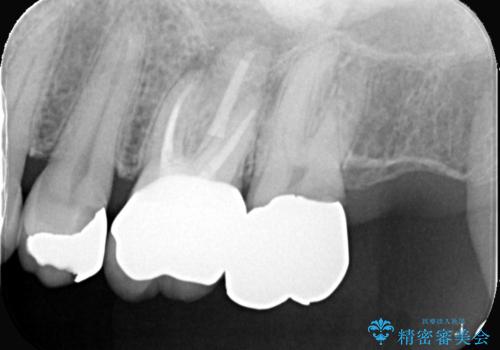

他院で治らなかった根管治療を精密治療で改善|MB2を発見し再治療

- 患者様は、他院で根管治療を受けていたが、なかなか治らず、より精密な治療を希望して当院を受診されました。マイクロスコープを使用して詳しく診断したところ、上顎第一大臼歯(6番)のMB2(第二頬側根管)の見落としが判明。このままでは感染が残り、再発のリスクが高い状態であるため、当院で精密根管治療を行う方針としました。

マイクロスコープを使用してMB2を確認し、感染源を徹底的に除去。その後、根管内を清掃・消毒し、高品質な充填材で密閉しました。従来の根管治療では見落とされがちなMB2の発見により、治療の精度が大幅に向上し、炎症の改善が期待できる状態となりました。患者様からは「治療後の違和感がなくなり、しっかり噛めるようになった」と喜びの声をいただきました。